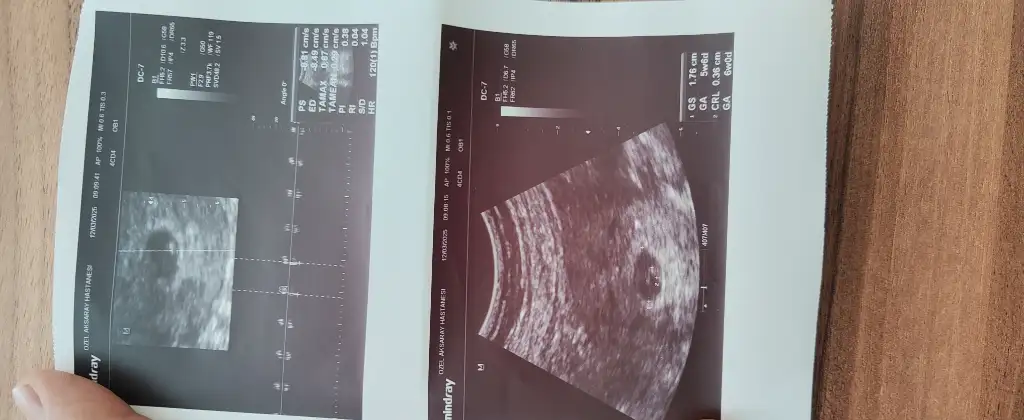

Merhaba rica edersem bana da bir tahminde bulunabilir misiniz 8+4 günlük karından ultrasonMerhaba kız olabilir

İnşallah beni de görürsünüzMerhaba kız olabilir